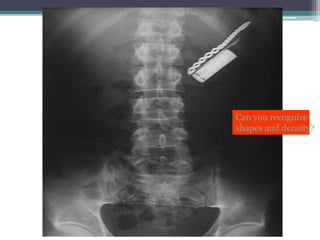

Can you recognize

shapes and density?